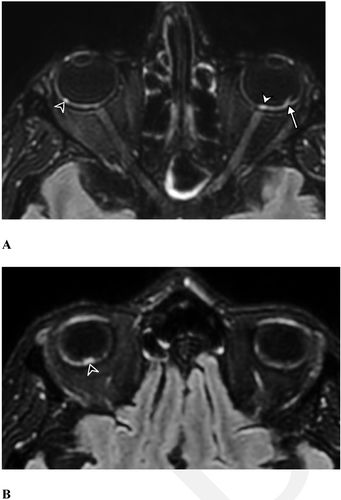

发表在《放射学》杂志上的一项新研究发现,重症新冠患者会出现一些眼部异常症状。“我们的研究表明,来自法国COVID-19队列的少数重症COVID-19患者眼底后极部有一个或几个结节,”研究主要作者、医学博士Augustin Lecler在一份新闻稿中说。“这是第一次使用MRI描述这些发现。”

这项研究是由法国神经放射学协会提出的,涉及129名经历过严重COVID症状的患者,其中大部分患者在ICU度过了一段时间,并进行了插管治疗。值得注意的是,研究人员承认他们的研究具有一定的局限性,因为没有对照组,而且评估患者的样本量相当低。